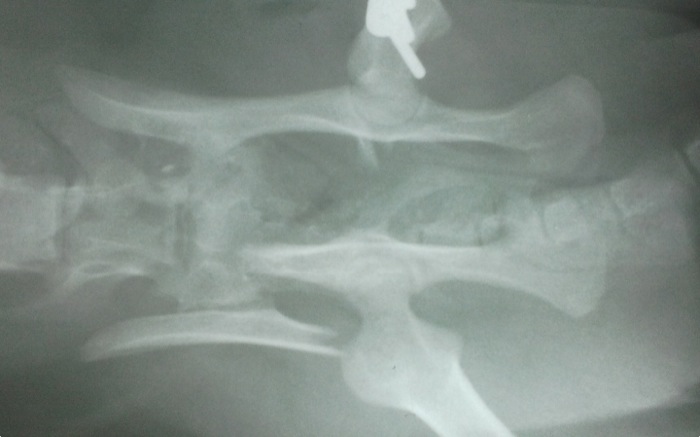

La unión es satisfactoria y se normaliza e tamaño del canal pélvico.

La radiografía de control es buena y el paciente se recupera también rápido de esta segunda intervención. Aunque a veces el operar en uno o dos tiempos un paciente suponga una duda normalmente se opta por esta solución cuando el estado físico es delicado como en este caso.